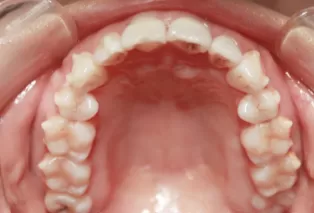

Femelle, âgée de 29 ans. Plainte principale: désalignement des dents, nécessitant une correction.

Encombrement et désalignement des dents maxillaires et mandibulaires, morsure croisée des dents 12 et 22 et désalignement de la ligne médiane.

Avant le traitement

Photos intra-orales